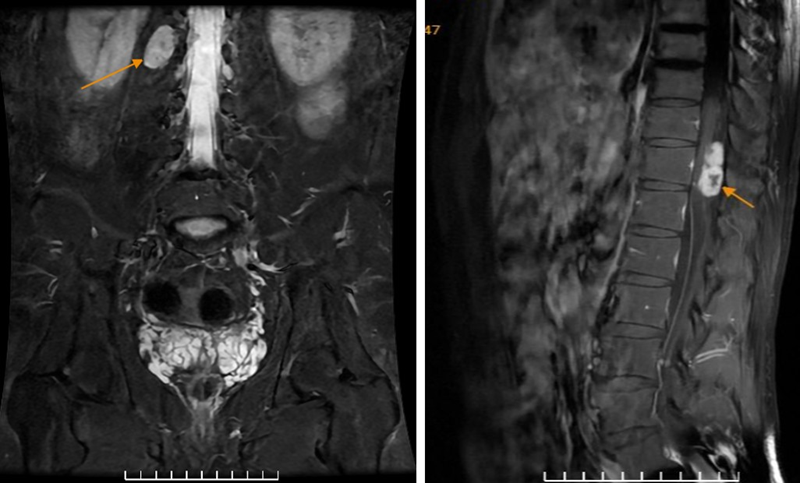

Hình ảnh khối trong ống sống vị trí T7, T11, cạnh phải lỗ tiếp hợp bên phải L1/2 trước và sau tiêm thuốc đối quang từ

Để xác định nguyên nhân, bệnh nhân được chỉ định chụp MRI có tiêm thuốc đối quang từ. Kết quả cho thấy, trên các chuỗi xung khảo sát chi tiết xuất hiện các khối trong ống sống tại mức đốt sống ngực T7, T11 và khối khu trú cạnh lỗ tiếp hợp bên phải mức L1/2. Các đặc điểm hình ảnh hướng đến chẩn đoán u bao dây thần kinh (Schwannoma) đa vị trí trong ống sống.